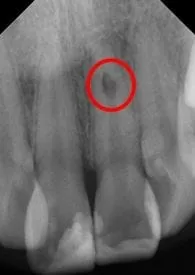

患者左側門牙牙根經由X光片檢查後發現牙根內吸收的狀況, 造成牙根內部的齒質破壞。

牙根內吸收是因為外傷或其他不明原因造成牙髓本身發生病變,而造成根管壁齒質的吸收。

因牙根內吸收的病人通常在臨床上大多無症狀,經常是在常規X光檢查時意外發現,所以此類牙齒不易獲得適切的照顧,治療時需要使用顯微根管處理,才可防止根管壁吸收的情況。